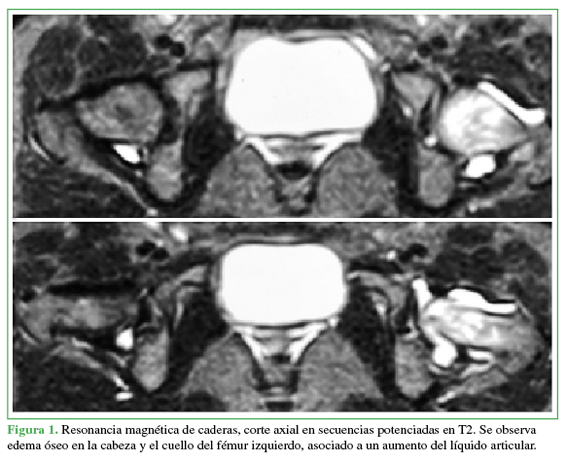

Acceso mediante suscripción PDF Acceso mediante suscripción PDF_EN (English) Acceso mediante suscripción Figura 1 Acceso mediante suscripción Figura 2 Acceso mediante suscripción Figura 3 Acceso mediante suscripción Figura 4 Acceso mediante suscripción Figura 5 Acceso mediante suscripción Figura 6 Acceso mediante suscripción HTML